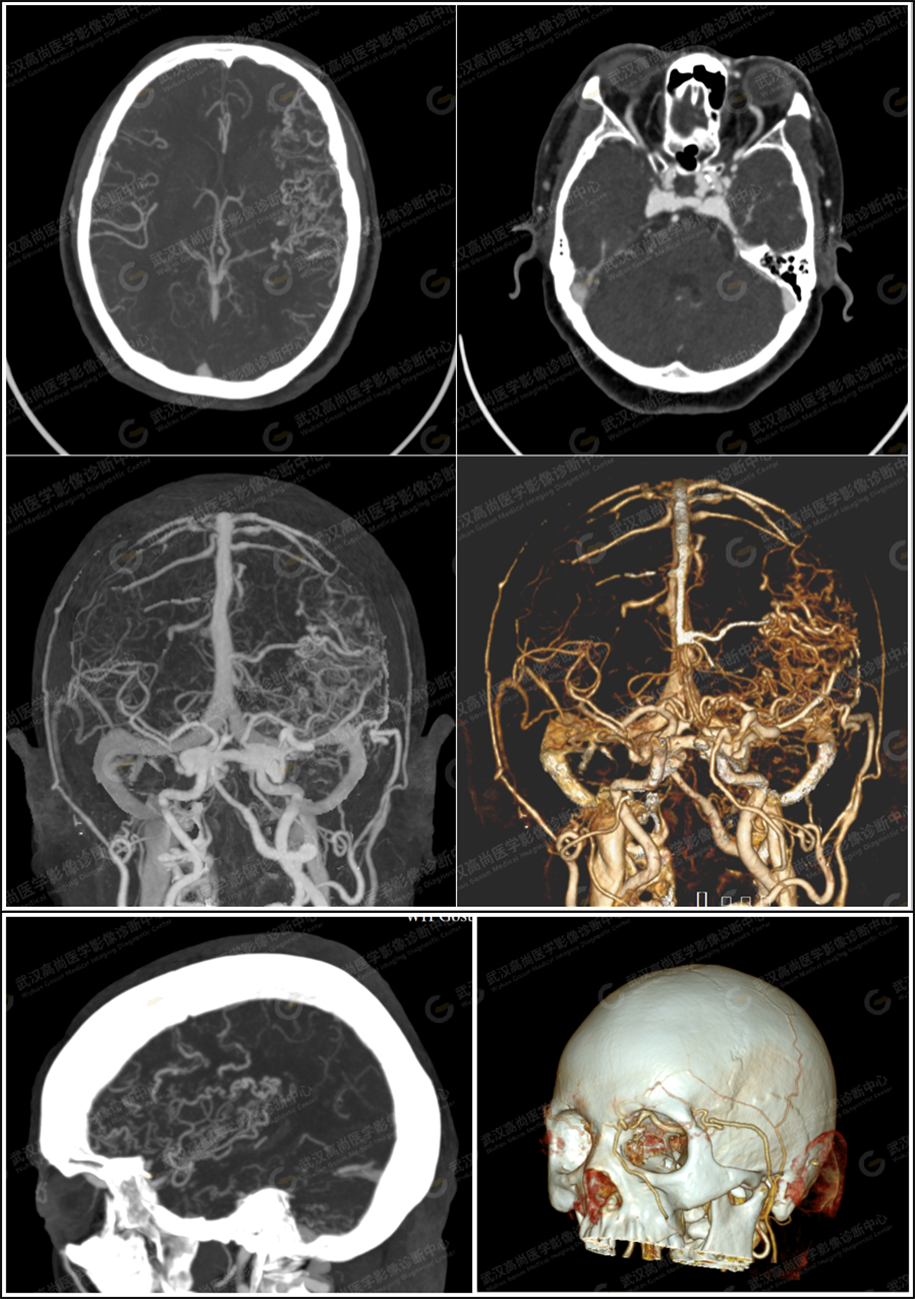

两天后申请头颅 CTA 检查,CTA 图像所示:

双侧颈内静脉、颅内各静脉窦提前显影,未见明确充盈缺损;双侧海绵窦体积扩大,可见迂曲扩张静脉提前显影,左侧为多,部分通向脑表面;双眼上静脉提前显影,迂曲增粗,左侧为著;大脑大静脉提前显影,明显增粗;大脑皮层静脉显示增多、轻度增粗;左侧额颞顶叶、左侧小脑半球见多发异常迂曲、扩张血管网影,呈毛线团状;右侧额颞叶血管轻度增多、迂曲。左侧颞浅动脉轻度增粗、迂曲。

CTA 提示:考虑硬脑膜动静脉瘘。